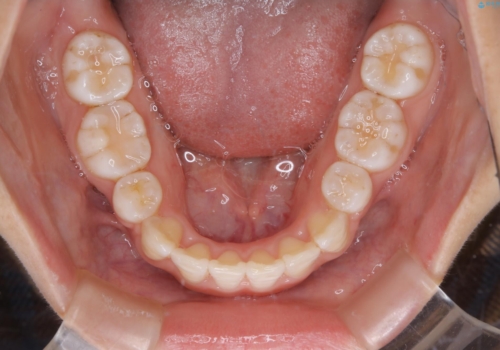

インビザライン単独での抜歯矯正治療

- 当院にてインビザライン治療を行っていた同僚の方からのご紹介でいらした方です。楽器を演奏されるとの事で、インビザラインによる矯正治療をご希望されました。治療の途中で一時的にワイヤー矯正に切り替える可能性もあることもご了承頂いた上で治療を行いました。

1日20時間以上、正しくインビザラインを使用して頂いたおかげで、ワイヤーに切り替えることなく矯正治療を終了することが出来ました。抜歯症例でしたが比較的短期間で見た目が劇的に改善し、大変喜んでいただけました。